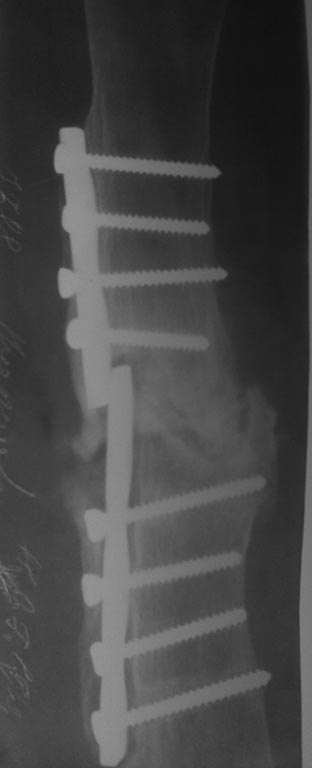

Снимки пожалуйста. Если рефрактура диафиза я бы произвёл реостеосинтез БИОС*м предварительно освежив концы (Это мысли в слух. А так надо посмотреть снимки, начиная с 3 летней давности. Узнать физическое и психоэмоциональное состояние бабушки прежде чем делать окончательный вывод).

Спасибо за ответ коллега. У больной физический и психический статус почти норма. Просто она хочет сама обслуживать себя. Она настаивает на операции, не смотря о возможные негативные стороны операции. У нас пока БИОС а не практиковали. И если заказать, обходится очень дорога.

Уважаемый Абдурашид! Спасибо большое за ответ.Там инфекции нет. просто не сращение перелома. мы находимся в Хорезме Узбекистан. Операцию отложили из за жары. планируем удаление пластины и освежение и фиксация большой пластины, как мостовидная, пластину установить будет или чуть спереди или чуть сзади чтобы избежать параллельных отверстии. С Уважением Кудрат Жаббаров!!!!!!!!!

Добрый день!Подберите стержень по диаметру и длине(Кюнчер,ЦИТО....)проще и надежней!

Простое освежение концов и шинирование пластиной(как вы пишите-мостовидная) не приводить к сращению! Если пациентка не платежеспособна, тогда лучше как пишет Олег-подходяший Кюнчер, ЦИТО. но после малоинвазивного удаления пластины, закрыто рассверлить канал и закрытый устойчивый остеосинтез как когда-то предлагал Охотский.

Если пациентка в состоянии , то лучше конечно БИОС, если что поможем, передайте привет Машарипову К. моя почта-abdurashid52.at@gmail.com